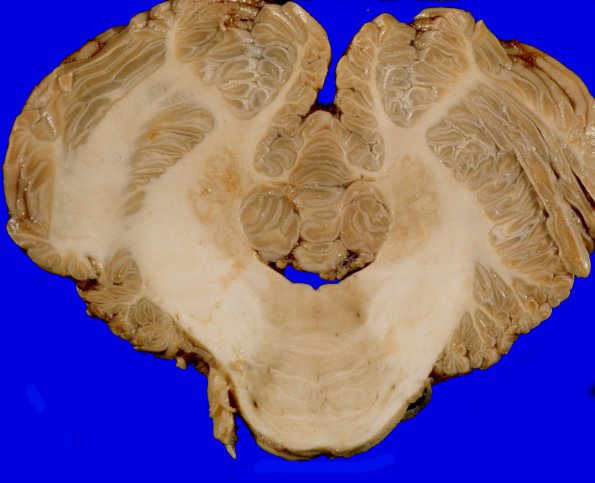

Pons/Medulla with attached cerebellar hemispheres